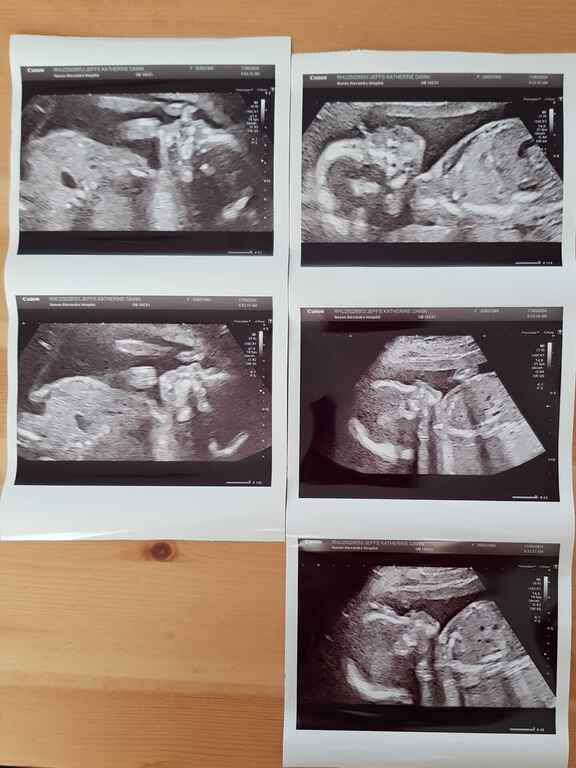

Photos 2024 January 21, 2024 · #photos#2024 « PreviousEmacs asynchronous copying using dired-async-mode Next »Opening Frequently Used Files More Efficiently using consult A new year, a new gallery! « PreviousEmacs asynchronous copying using dired-async-mode Next »Opening Frequently Used Files More Efficiently using consult